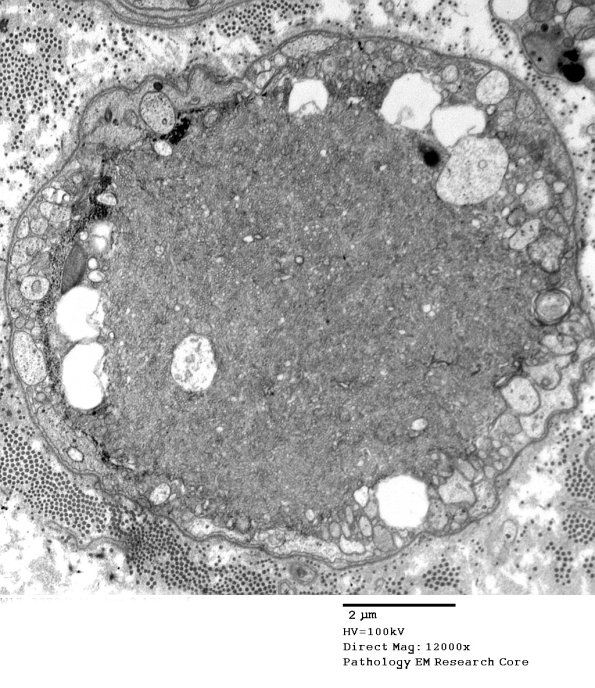

2C11,12 A similar result is seen in this axon.